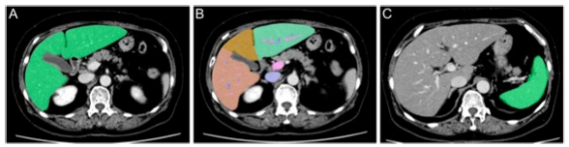

圖 一位患有肝癌的67歲婦女的CT圖像。A TLV的軸位圖像。原始數(shù)據(jù)被手動(dòng)發(fā)送到工作站后,TLV實(shí)現(xiàn)自動(dòng)測(cè)量。B 分割的TLV軸位圖像。鐮刀狀韌帶和中央肝靜脈被用作標(biāo)志,分別從內(nèi)側(cè)和外側(cè)分離出II、III和IV。C SV的軸位圖像。在這個(gè)工作站(ver5.5)中,SV是手動(dòng)測(cè)量的